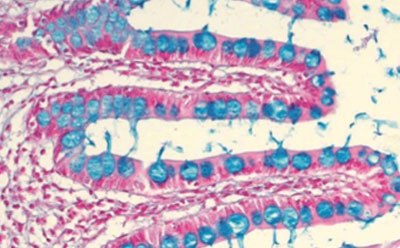

From consistent routine and special stains, to reliable Cell Marque™ IHC primary antibodies, universal reagents, control slides and cell lines, we provide efficient, precise solutions for research and clinical pathology laboratories. We developed trusted staining solutions and ready-to-use test kits, as well as Biological Stain Commission (BSC) certified dyes, centrifugation media, and in vitro diagnostics immunohistochemistry (IHC) antibodies and reagents.

Our complete line of solvents and fixatives for microscopy sample preparation, mounting media for routine and fluorescent applications, and tissue quality control slides allows increased stability, ease of use, and reproducibility of results. Our products are manufactured following cGMP practices, and our IVD stains and kits comply with ISO 13485 and CFR 820. Our pathology lab reagents are IVD-registered and CE-certified where required.

Browse our comprehensive tissue diagnostics and microscopy portfolio with routine, special, and advanced staining solutions for hematology, cytology, histology and bacteriology.